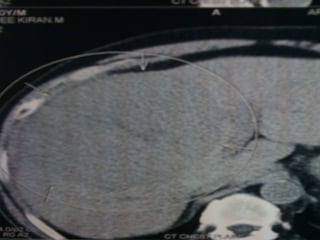

• USG ABDOMEN- HETEROECHOIC LESION

RIGHT LOBE OF LIVER-11.5×10.5 CM –

• IMPRESSION- HCC Rt. LOBE OF LIVER

INVESTIGATIONS • CBC- NORMAL •LFT- S. BILIRUBIN- 1.3 DIRECT- 0.9 ALK.POS- 80 T.PROT- 6.8 ALB- 3.7 • RFT- NORMAL • HbSAG- NEGATIVE • ANTI HCV- NEGATIVE • HIV I & II- NEGATIVE • ALPHA-FETO PROTEIN- 1.62 IU/ml • USG ABDOMEN- HETEROECHOIC LESION RIGHT LOBE OF LIVER-11.5×10.5 CM – • IMPRESSION- HCC Rt. LOBE OF LIVER